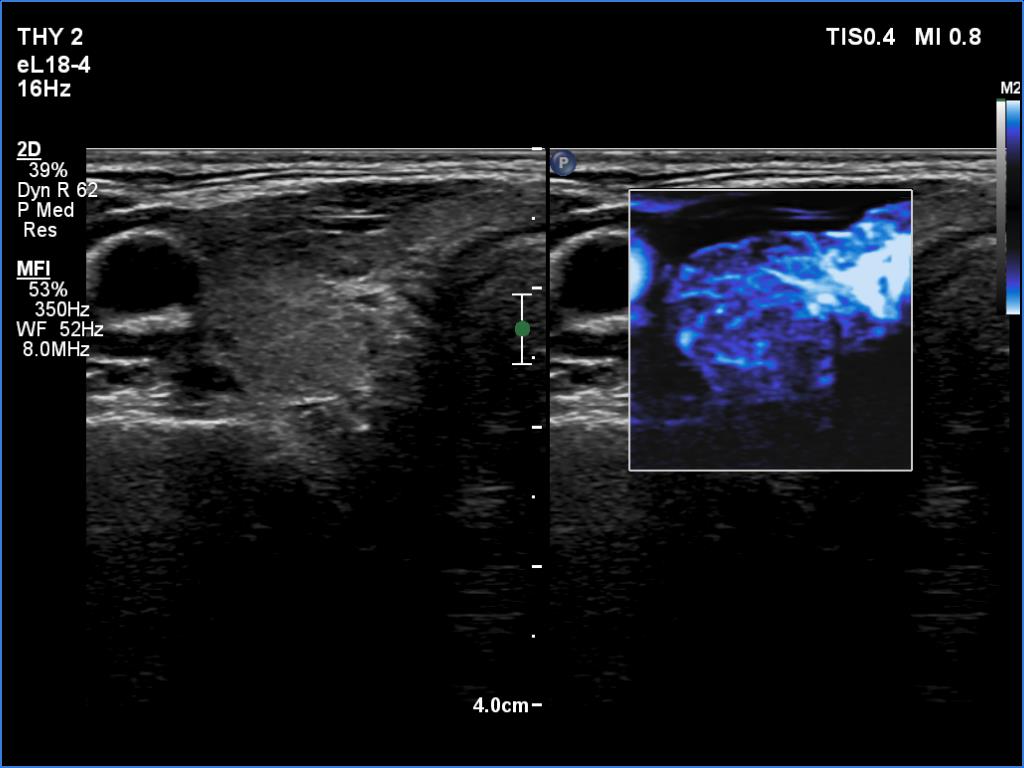

Examination a year after the first visit (ultrasonographic picture 4)

Right lobe, transverse scan, microflow imaging. This pattern became also similar to that seen at the first examination.